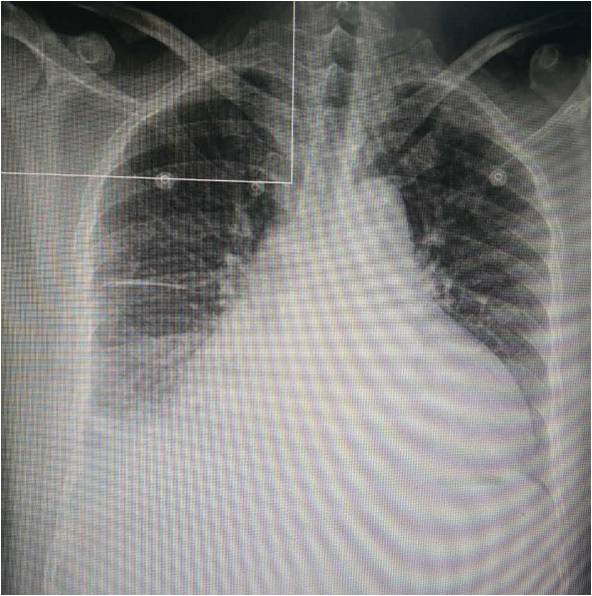

胸片:心影增大,右侧胸水,肺淤血改变,右下肺纹理增多炎变